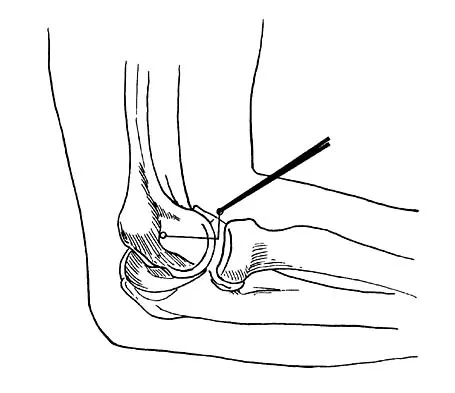

What neurovascular structure is in closest proximity to the probe in the arthroscopic view of the elbow shown in Figure 50?

Explanation

What three structures are considered the primary constraints necessary for elbow stability?

Explanation